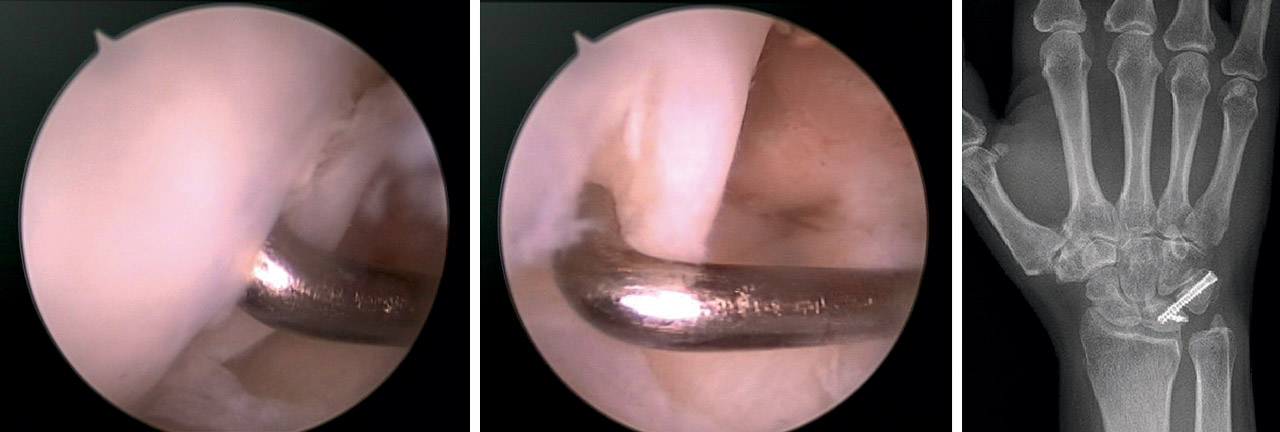

• En fracturas con componente principalmente articular se realiza artroscopia de inicio y la fijación de la fractura se efectúa visualizando directamente la reducción “fragmento a fragmento”, sosteniéndolos en empalizada con agujas de Kirschner (AK) o tornillos percutáneos, comprobando de forma directa la reducción de la superficie articular (Figura 5). No se realizó fijación con placa volar en estos casos.

• En fracturas metafisarias y patrón mixto se realizó RAFI con placa volar y posteriormente se realizó la artroscopia para comprobar el estado de la articulación y el balance de partes blandas, fijando los fragmentos articulares provisionalmente con AK y, una vez comprobada la correcta reducción, se colocan los tornillos definitivos.

Fragmentos osteocondrales libres

Se realizó reducción y fijación en los casos viables, o resección artroscópica en caso contrario. La viabilidad del fragmento se estableció en función de la dimensión, la integridad, la fragmentación del cartílago articular y la posibilidad de fijación.

En casos de fragmentos osteocondrales con suficiente entidad, se intentó la reducción artroscópica directa y la fijación con tornillo ocultable percutáneo o con varillas de material reabsorbible(32). De lo contrario, fueron extraídos.